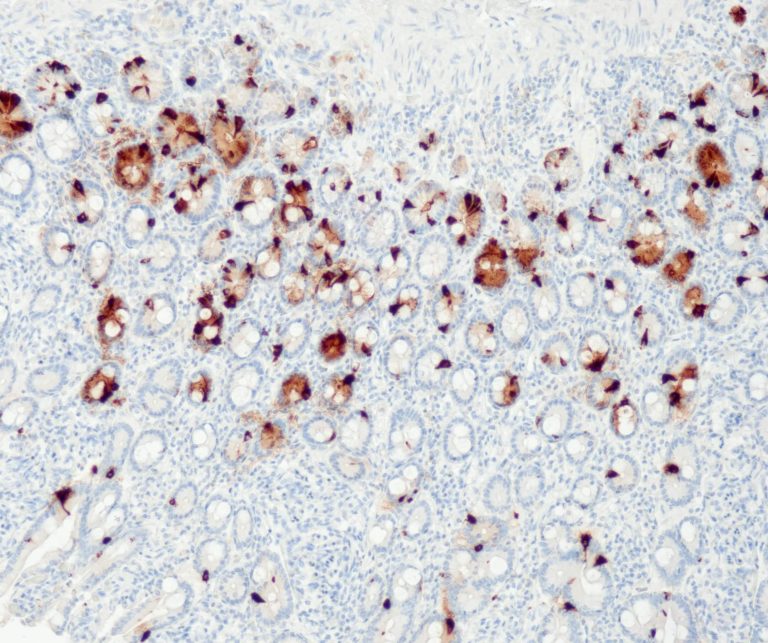

Gastrointestinal (GI) Pathology